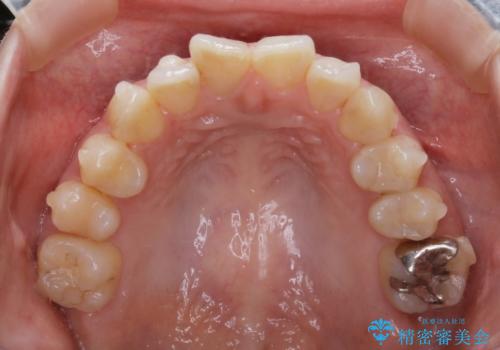

虫歯の治療などが必要な部位がある場合には矯正治療に先立ち全体の状態をよくする術前治療が行われます。

当院では矯正治療を主訴にご来院された方は治療開始前に必ず精密検査を受けていただきます。

ご本人は症状もなくご自覚がなくても実は歯周病が進行していたり、根管治療が必要な歯が見つかるということもあります。

基本的にはそういった歯周病・虫歯に対しての治療は矯正治療開始前に完治させておく必要があります。これは、矯正装置装着後は清掃不良になりやすく虫歯の進行が早まったり、歯を移動させることで歯周病や根尖病巣が悪化する恐れがあるためです。